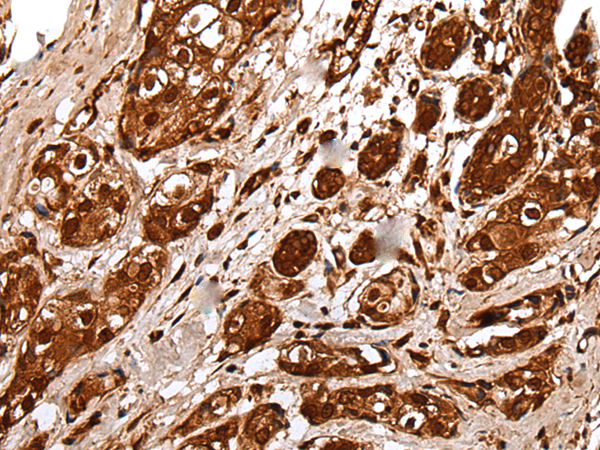

分类: 科研抗体货号: P09304别名: CIR1; UEV1; CROC1; UBE2V; UEV-1; UEV1A; CROC-1应用: WB,IHC反应种属: Human, Mouse